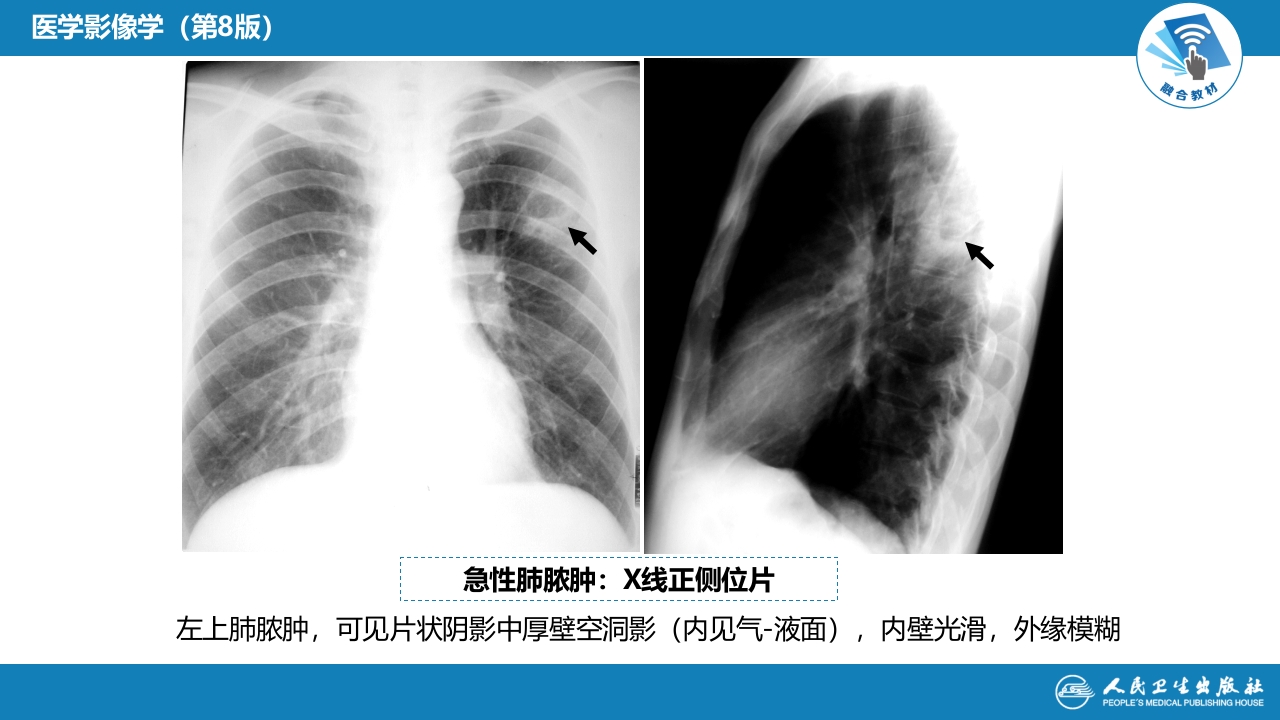

第四章 呼吸系统 第四节 疾病诊断-肺脓肿、肺结核